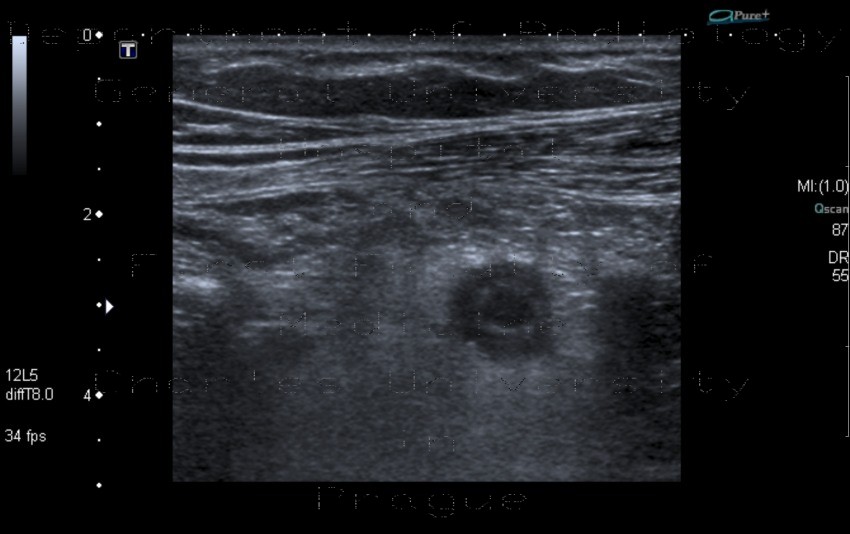

Appendicitis is a condition in which the appendix becomes inflamed, swollen, or infected, causing pain in the lower right side of your torso. 19.11.2021 · appendicitis is inflammation of the appendix. Appendicitis is when your appendix becomes sore, swollen, and diseased. Doctors use an ultrasound as the first imaging test when checking for possible appendicitis in infants, children, young adults, and pregnant women. 14.08.2005 · sturm ejc, cobben lpj, meijssen mac, werf sdj, puylaert jbcm.

Ultrasound can identify an enlarged appendix or an abscess.

Ultrasound with its lack of ionizing radiation should be the investigation of choice in young patients. However, the identification of a normal appendix is more problematic, and in many instances, appendicitis cannot. With a competent user, ultrasonography is reliable at identifying abnormal appendices, especially in thin patients. Lets the doctor see internal organs as they work and checks how blood is flowing through different blood vessels. Doctors use an ultrasound as the first imaging test when checking for possible appendicitis in infants, children, young adults, and pregnant women. The aim of this investigation was to answer the question, whether the results of these studies depend on study design, the investigating clinical department, or the number of ultrasound … Both, studies with excellent and such with disappointing results have been published. 18.03.2022 · an ultrasound is a painless procedure that uses sound waves to provide images to identify organs within the body. You must seek care right away.

Appendicitis Ultrasound / Acute Appendicitis On Ultrasound Sagittal A And Transverse B Download Scientific Diagram. Ultrasound with its lack of ionizing radiation should be the investigation of choice in young patients. If you have appendicitis symptoms and your blood test shows a high white cell count, your provider may order an abdominal ultrasound and/or a ct scan to help confirm a diagnosis. Lets the doctor see internal organs as they work and checks how blood is flowing through different blood vessels.